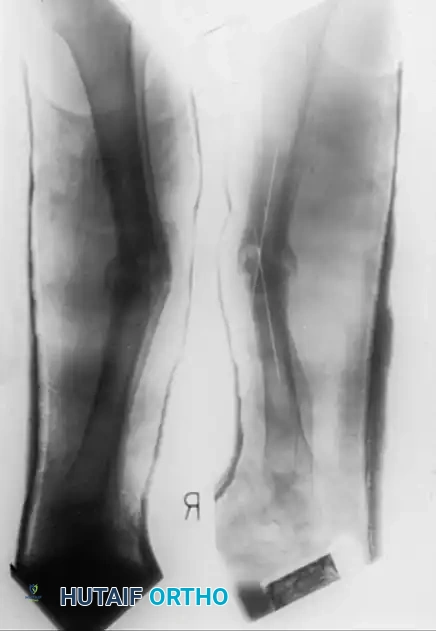

The absolute prerequisite for successful TSF application is pristine preoperative imaging. True orthogonal (anteroposterior and lateral) views of the entire limb are mandatory.

These orthogonal views are used to:

1. Completely characterize the plane and extent of angulation and translational deformities.

2. Determine the correct ring diameter based on preoperative sizing of the limb (allowing for postoperative swelling).

3. Define the "mounting parameters" (the exact position of the reference ring relative to the bone).